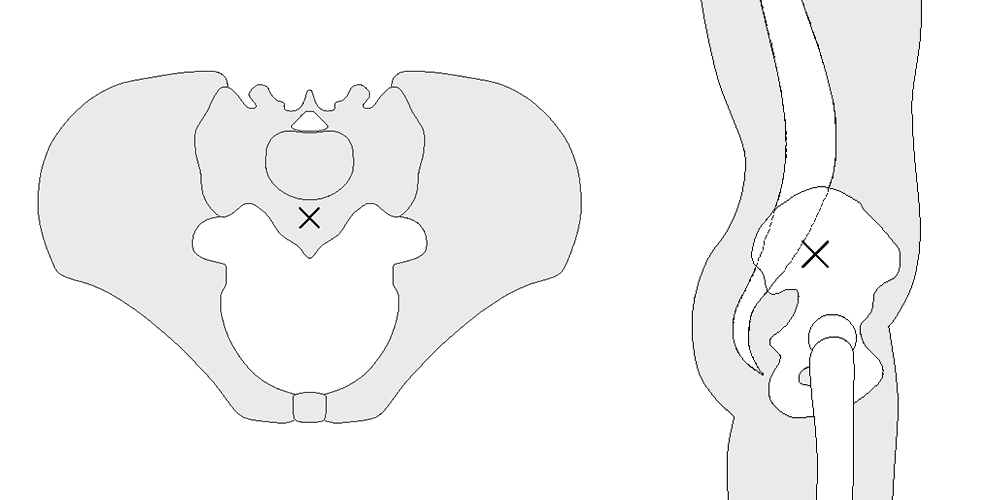

O peso corporal pode ser representado como uma carga aplicada com um braço de alavanca que se estende do centro de gravidade do corpo ao centro da cabeça femoral. O centro de gravidade corporal é variável em função do ortostatismo, decúbito, posição sentado, entre outras, conforme a posição da pelve. Geralmente o centro de gravidade em ortostatismo fica ligeiramente anterior a S2 (Fig. 3) (7).

A musculatura abdutora, atuando sobre um braço de alavanca que se estende da face lateral do grande trocânter ao centro da cabeça femoral, tem que exercer um momento igual para manter a pelve na horizontal quando em apoio sobre uma perna somente (2,5x peso corporal) e um momento maior ainda para inclinar a pelve para o mesmo lado quando em marcha ou correndo. A carga sobre a cabeça femoral é em torno de 3,5 a 5x o peso corporal em marcha e pode atingir até 10x ao correr ou saltar. O posicionamento cirúrgico pode alterar estes braços de alavanca através da modificação de offsets e osteotomias do grande trocânter e sua posterior fixação (Fig. .4) (2,7).